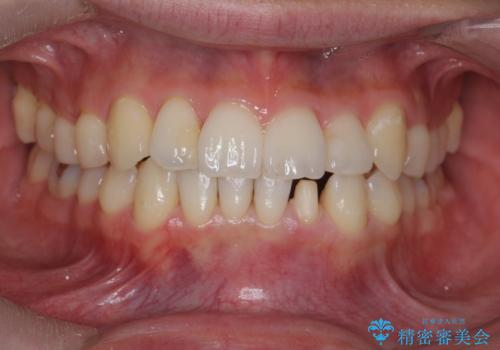

下の前歯が欠けている セラミックで審美的に エアフローで着色除去も

- 左下の前歯が削れて欠けているとのことで、治療希望されました。

プラスチックで詰めたものが度々取れてしまうとのこと。

しみないようであれば機能的にはそこまで問題はないと説明しましたが、審美的な治療をご希望でした。

プラスチックの詰め物と比較して、変色もなく、脱離もしにくいセラミッククラウンで修復しました。

前歯のステインはエアフローという方法で綺麗にクリーニングしています。